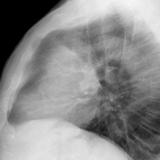

Case 8b Thymoma Lat

Date: 03/27/2009

Views: 14097